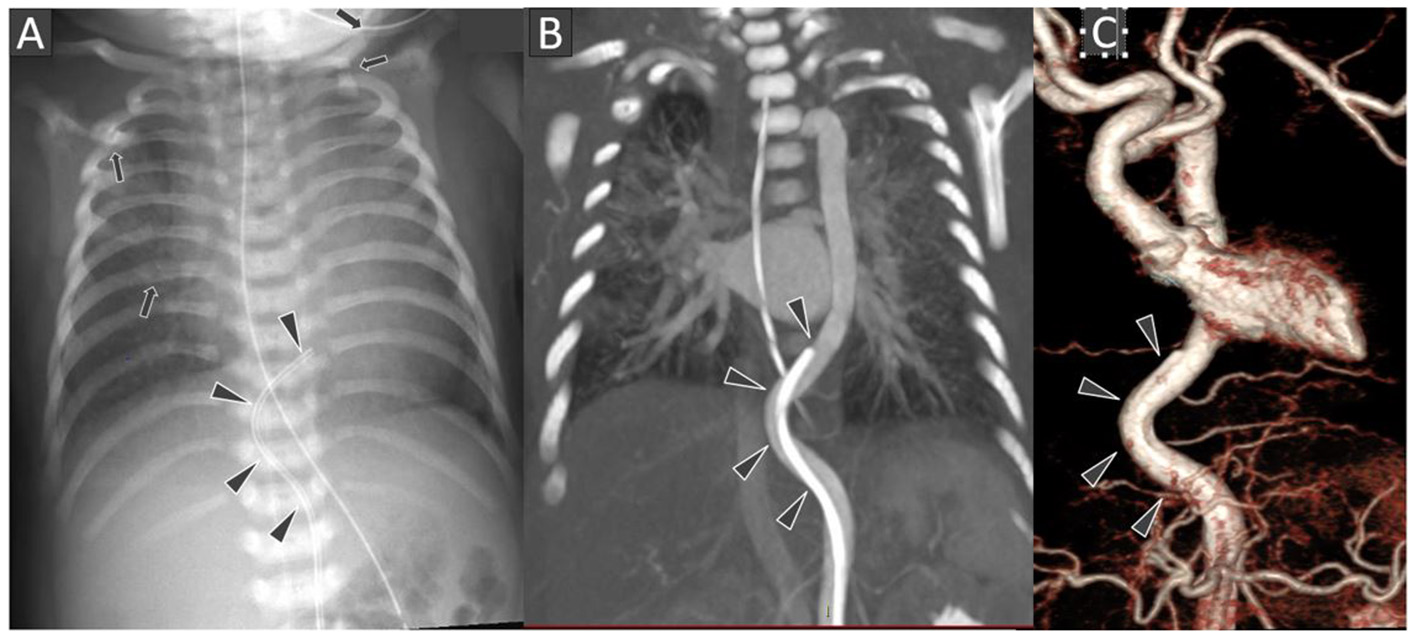

Figure 1

Frontal chest radiograph (A) shows the tip of the umbilical arterial catheter (UAC) at the level of T8 vertebral body with curved configuration of its terminal portion (black arrowheads). Several rib and left clavicular fractures (black arrows) are also noted in the bony thoracic cage. Chest CT Angiography coronal multi-planar reconstruction image at the level of thoraco-abdominal aorta (B) and 3D surface shaded display image of the thoraco-abdominal aorta (C) showing the arterial tortuosity with distal end of the UAC location in descending thoracic aorta.

The umbilical artery catheter (UAC) (Figure 1) was incidentally noted to have a tortuous course on radiograph on D5 of life (Figure 2A). A Computed Tomography Aortogram (CTA) was performed to evaluate the aortic arch anatomy. CTA confirmed the findings of a left-sided aortic arch with a dilated and tortuous right brachiocephalic artery forming a hairpin loop before bifurcating into the right subclavian and common carotid arteries (Figures 2B,C). The left common carotid and subclavian arteries arose from the hypoplastic transverse arch. The thoraco-abdominal aorta, and branches of the coeliac axis, appeared dilated and tortuous corresponding with the tortuous course of UAC. The branch pulmonary arteries appeared unusual as well, with proximal segments coursing parallel to each other before branching to the left and right, respectively (Figures 2A–C). The pulmonary veins were normal (Figure 2D). The abdominal aorta and the celiac axis branches were dilated and showed tortuosity. The UVC was also tortuous as evidenced in the abdominal roentgenogram.